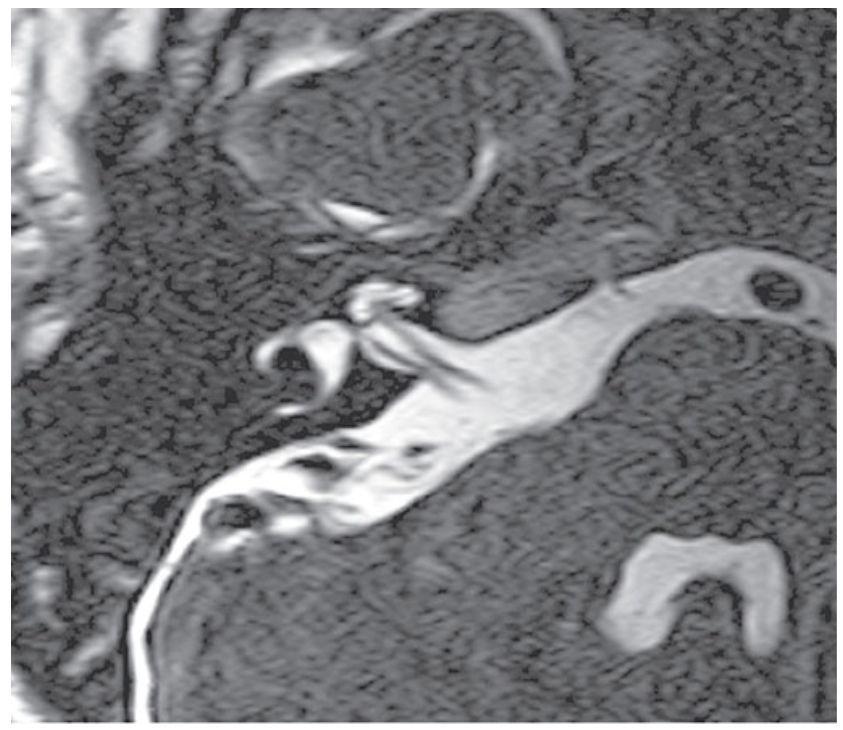

What does this image show?

Axial DRIVE image through the right internal auditory meatus